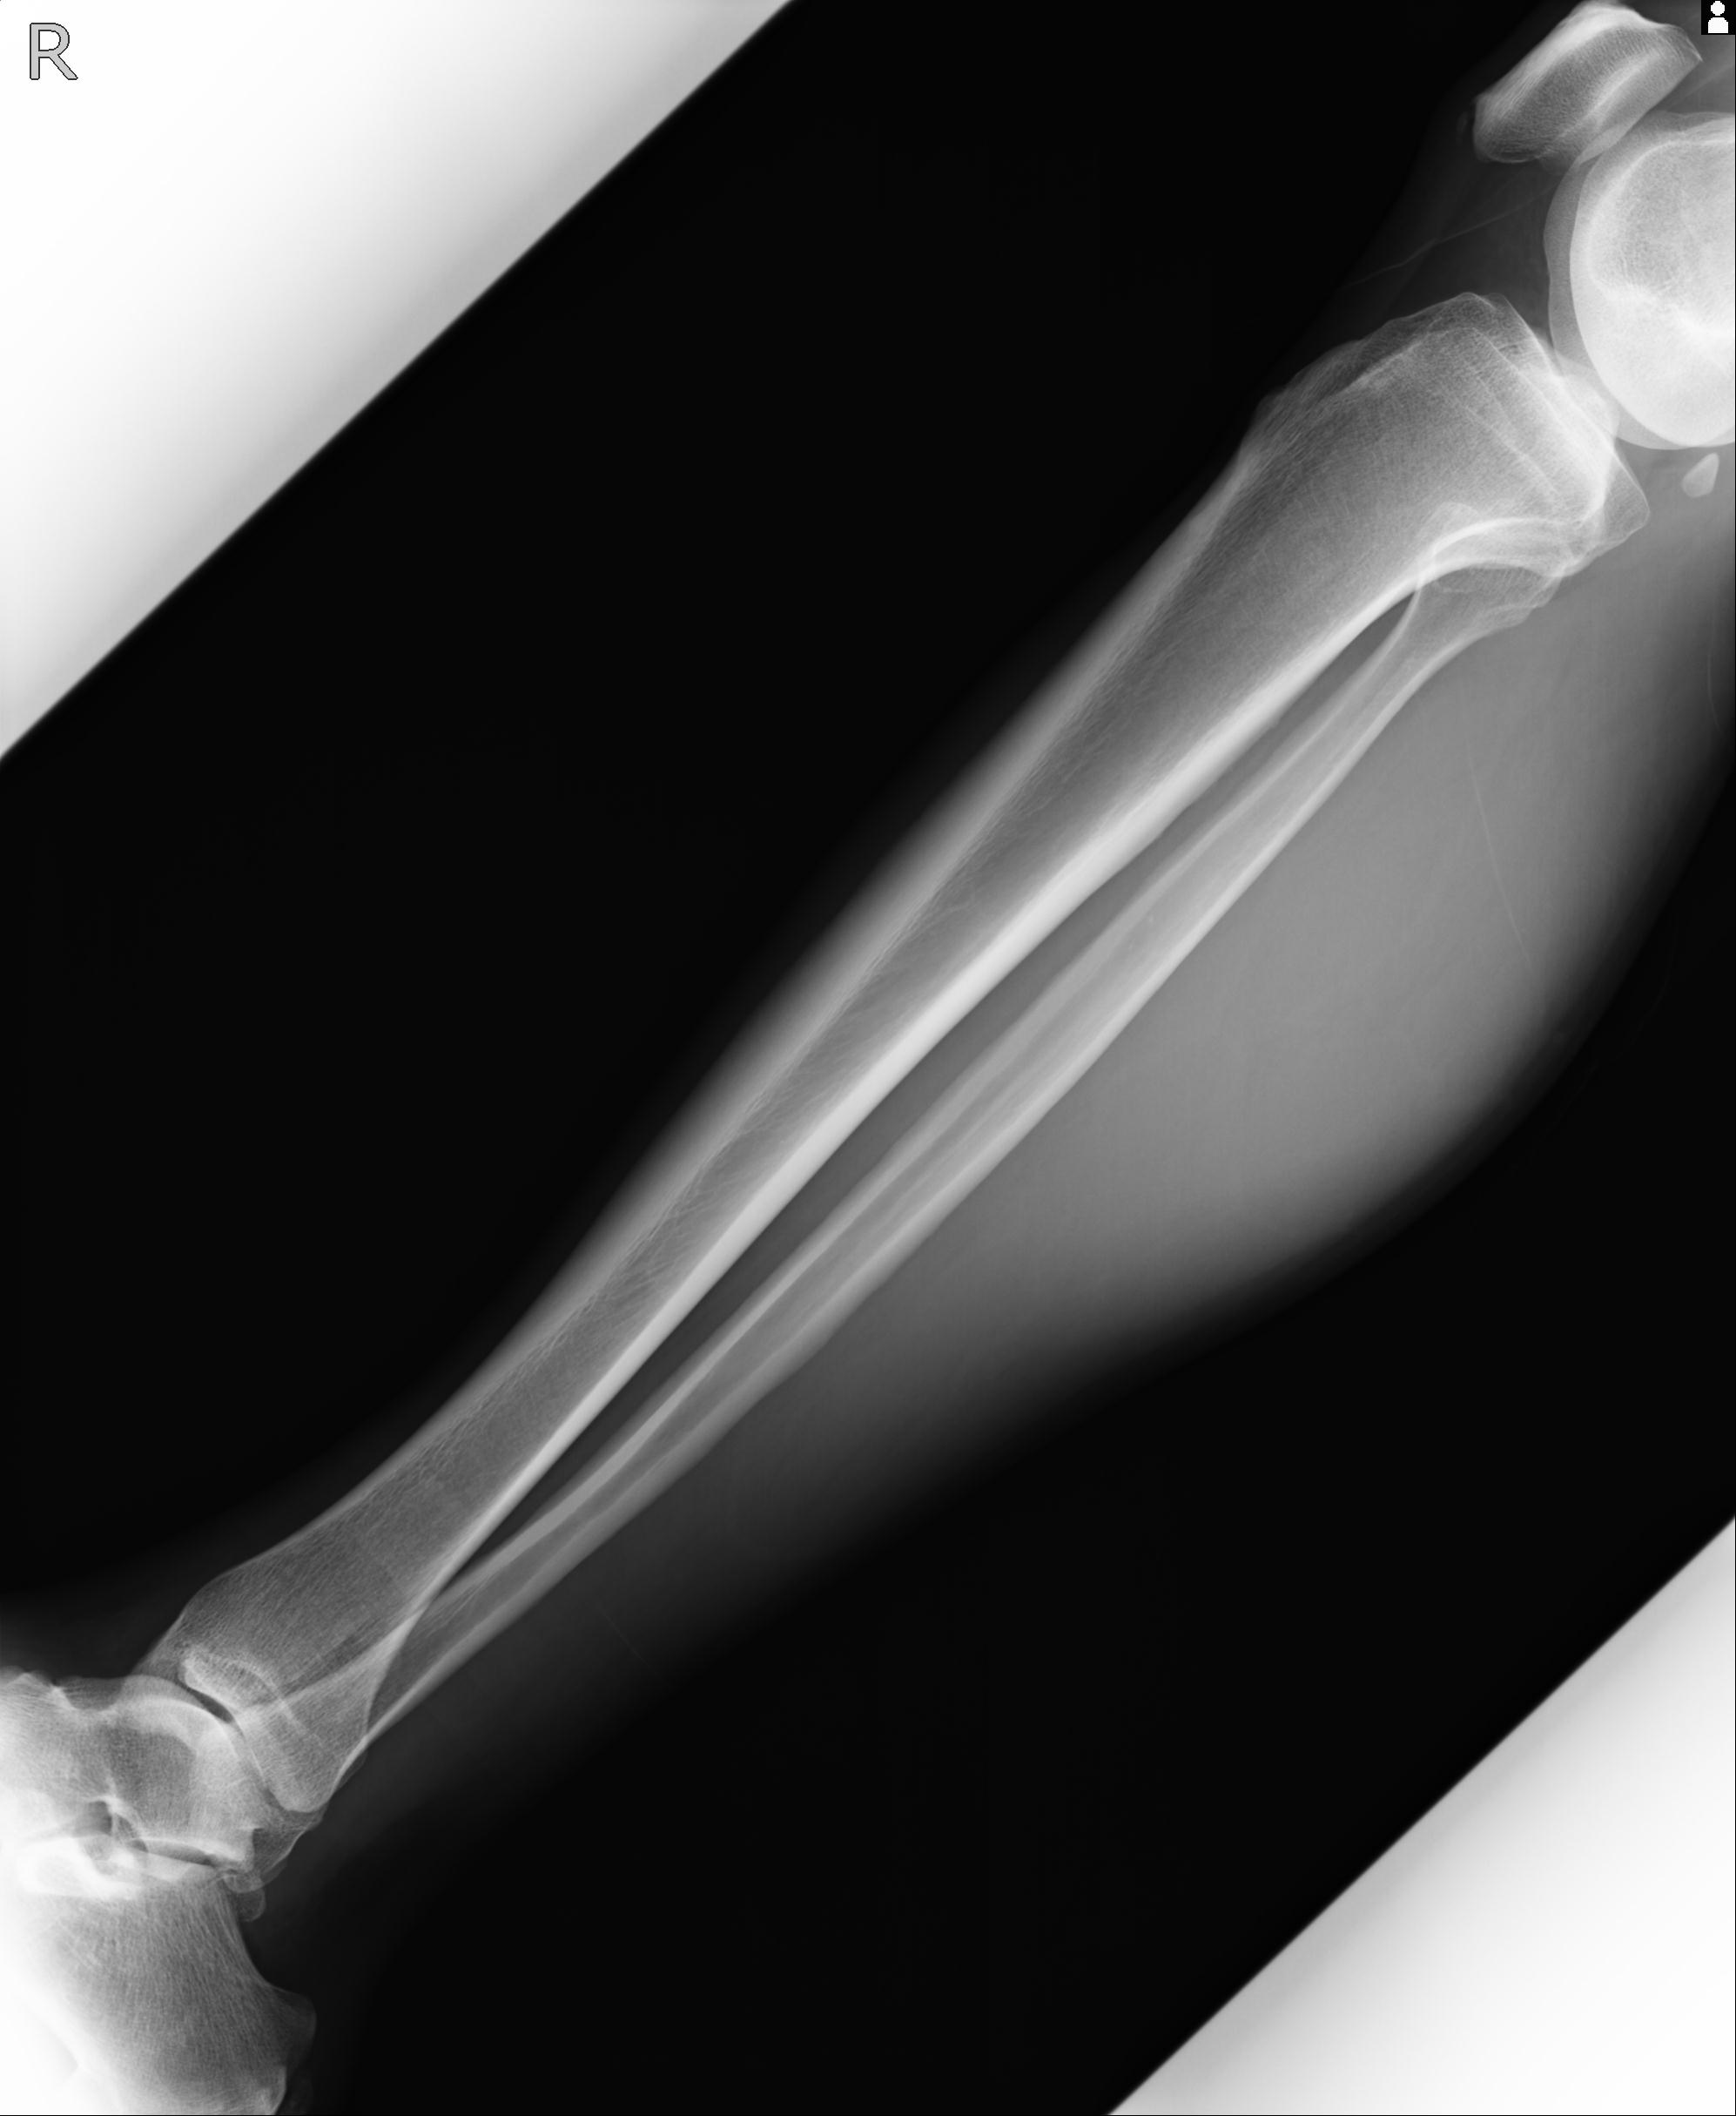

102803 1/12(キウスなし) 1/27 左下腿 4R 30歳女性 左脛骨軸内釘